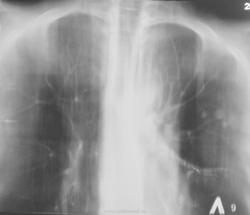

Вызванный в терапевтическое отделение фтизиатр (для консультации) назначил томографию.

Решили "чиркнуть" боковые томограммы.

Вызванный в Т.О. фтизиатр (для консультации) назначил линейную томографию.

Коллега фтизиатр находится в растрепанных чувствах, настаивает на томографии в прямой проекции.